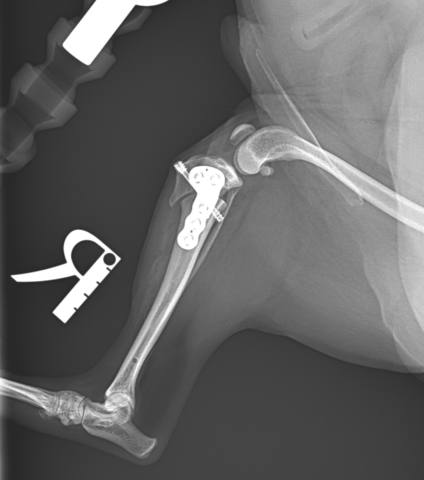

チワワ11歳4kgの右前十字靭帯完全断裂に対してリハビリテーションを開始しました。